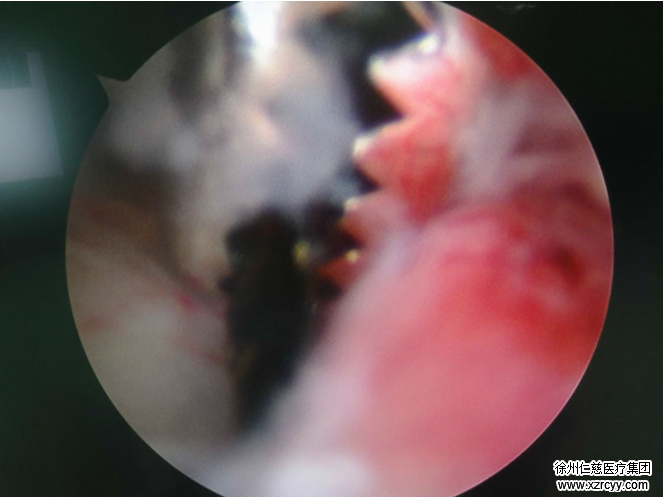

齐主任在腕关节镜手术中

3月18日,在腕关节镜的直视下,齐主任确定了异物的准确位置。半小时后,一枚比7号针头大两倍(芝麻粒大小)的铁屑,被成功取出。手术顺利进行,休养2天后,王先生便出院回家。